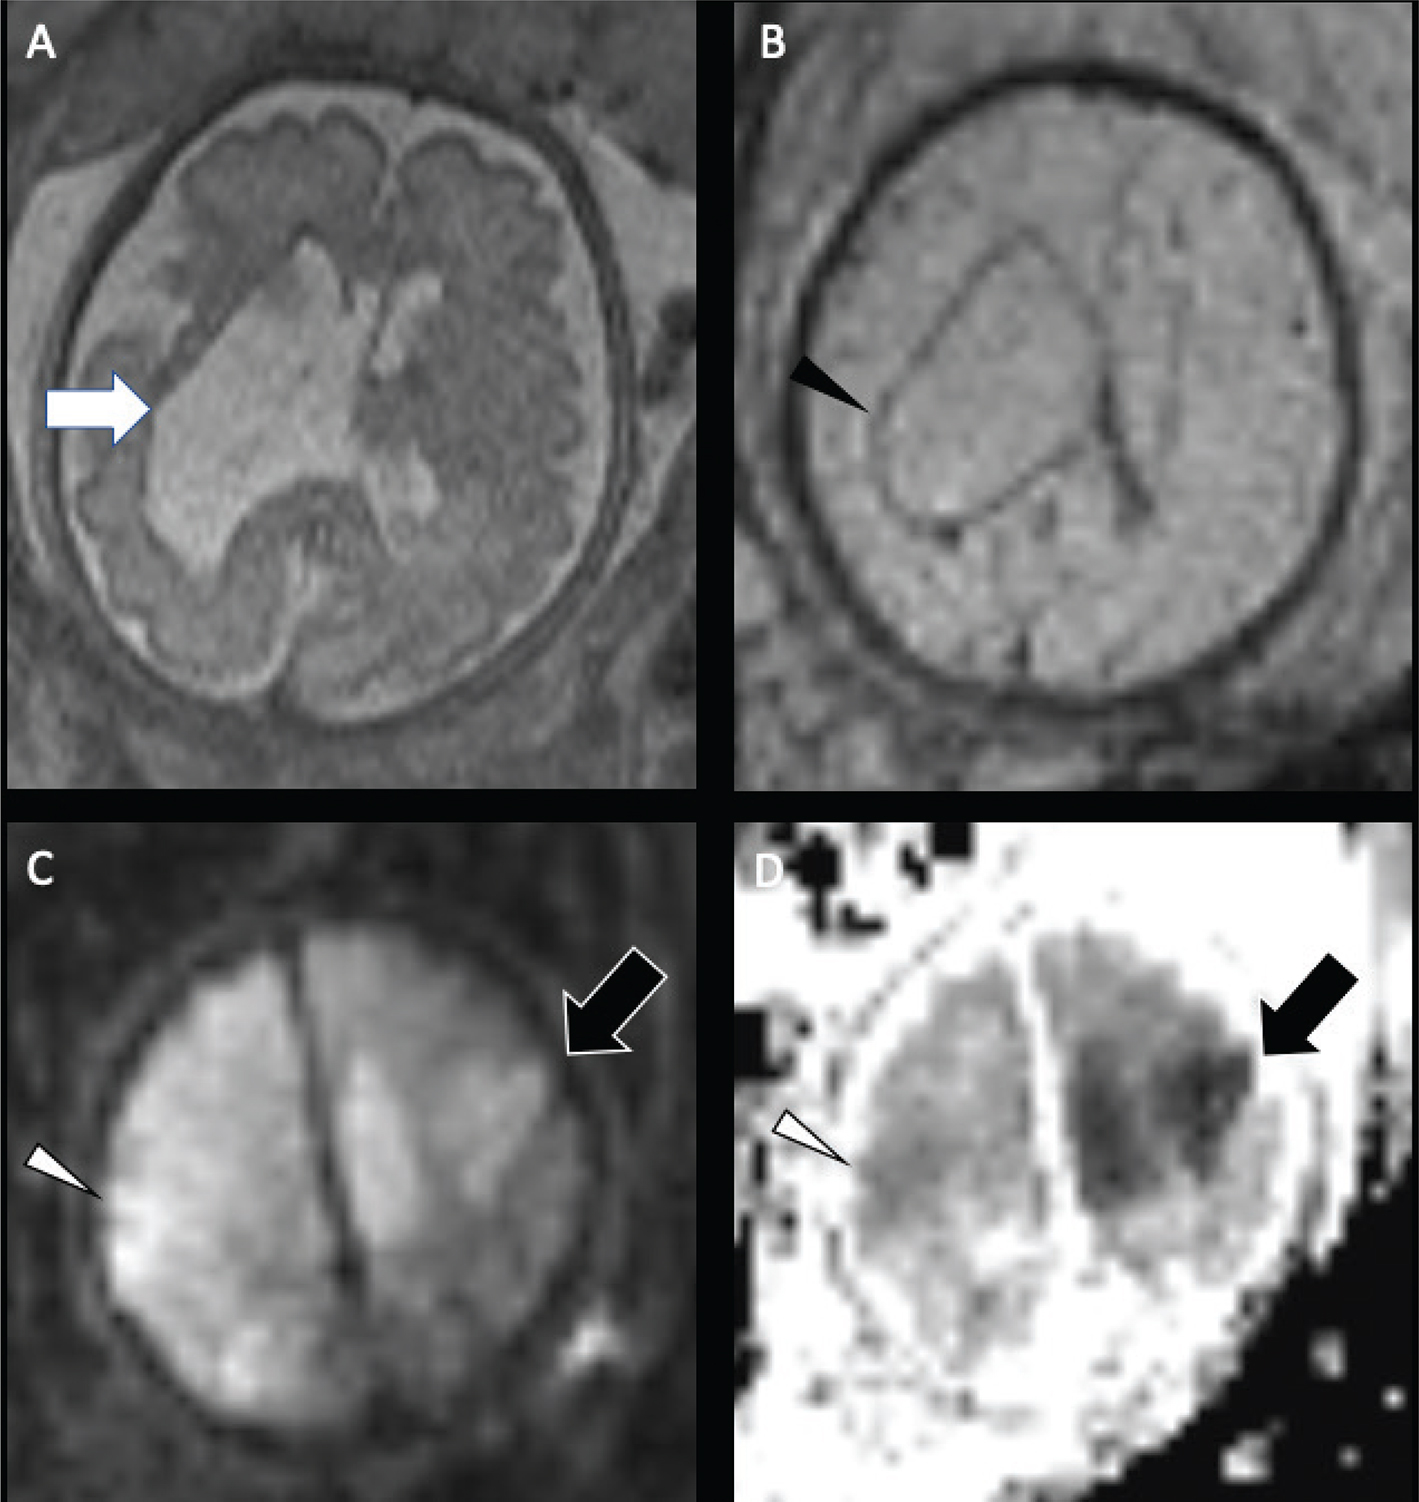

The chronic stage (beginning by 3 weeks) is characterized by volume loss and varying degrees of gliosis. The final appearance of the infarct is related to the timing of insult, the maturity of the infarcted brain, and the degree of astrocytic response to injury, and may span from none (infarct earlier in gestation) to mild (infarct later in gestation and early prenatal period). If injury occurs before 20 weeks of gestation, schizencephaly will often develop, with the cleft lined by dysplastic gray matter. Porencephaly results when the insult occurs between approximately 20 and 24 weeks from liquefactive necrosis, appearing as a smooth-walled, fluid-filled cavity isointense to CSF that may or may not communicate with the ventricular system. The surrounding white matter typically demonstrates normal signal. Encephalomalacia and gliosis results when the insult occurs in the late second trimester and onward, as the brain is able to mount an astrocytic response to injury, and demonstrates surrounding parenchymal signal abnormality, best depicted on FLAIR (Figure 6).

Fig 6

Figure 6. Presumed perinatal ischemic stroke (PPIS). A 10-month-old boy presented with early hand preference and medically refractory epilepsy. Axial T2-weighted (A) and coronal FLAIR (B) images demonstrate chronic infarction with liquefactive changes in the left MCA territory (white arrow) suggesting early injury, with associated decreased perfusion (black arrow) on ASL (C). Case courtesy of Dr. Tamara Feygin, Department of Radiology, Children’s Hospital of Philadelphia.

The incidence of perinatal hemorrhagic stroke is approximately 1 in 6000–9000 live births (6871). Compared with PIS, fairly little is understood about its risk factors, etiologies, and outcomes. While intraventricular hemorrhage in premature neonates originates from a fragile germinal matrix, the mechanisms responsible for late preterm and term hemorrhagic strokes remain unclear, and the majority are described as idiopathic (69, 70). In term infants, isolated intraventricular hemorrhage is less common than intraparenchymal hemorrhage and, if present, may be the result of CSVT (7274). Causes of hemorrhagic stroke include congenital and acquired coagulopathy, CSVT (particularly cerebral medullary veins thrombosis), vascular malformations, and hemorrhagic conversion of ischemic infarct (arterial or venous) (69). Hemorrhagic disease of the newborn is more prevalent in infants who have not received vitamin K at birth and in infants of mothers taking blood thinning medications, such as warfarin, phenytoin, or barbiturates, during pregnancy (75, 76). Acquired coagulopathies include neonatal alloimmune thrombocytopenia or disseminated intravascular coagulation. Some genetic arteriopathies associated with both fetal and neonatal hemorrhagic stroke include collagen IVA and JAM3 mutations, which can appear identical to hemorrhagic venous infarctions (7784). In addition to hemorrhages occurring later in life, fetal and neonatal patients may present with subpial hemorrhages (Figure 8), which may be related to local venous thrombosis or birth trauma (8587). In these cases, blood is seen between the pia mater and the displaced brain parenchyma, often accompanied by venous infarction and subarachnoid or parenchymal blood.

Fig 8

Figure 8. Subpial hemorrhage. A 17-day-old female with hypoplastic left heart syndrome status post Stage I Norwood with BT shunt. Coronal sonographic images (A) shows a heterogeneous lesion in the right temporal lobe. Axial non-contrast CT (B) shows the lesion to be a mixed intensity peripheral lesion in the right temporal lobe. T1- (C) and T2-weighted (D) images demonstrate a subpial hematoma in the right temporal lobe.